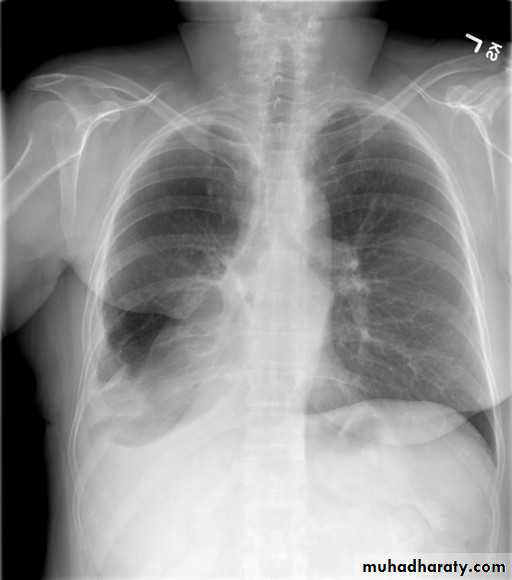

Pneumothorax

Patient with fever, rigor and dyspnea